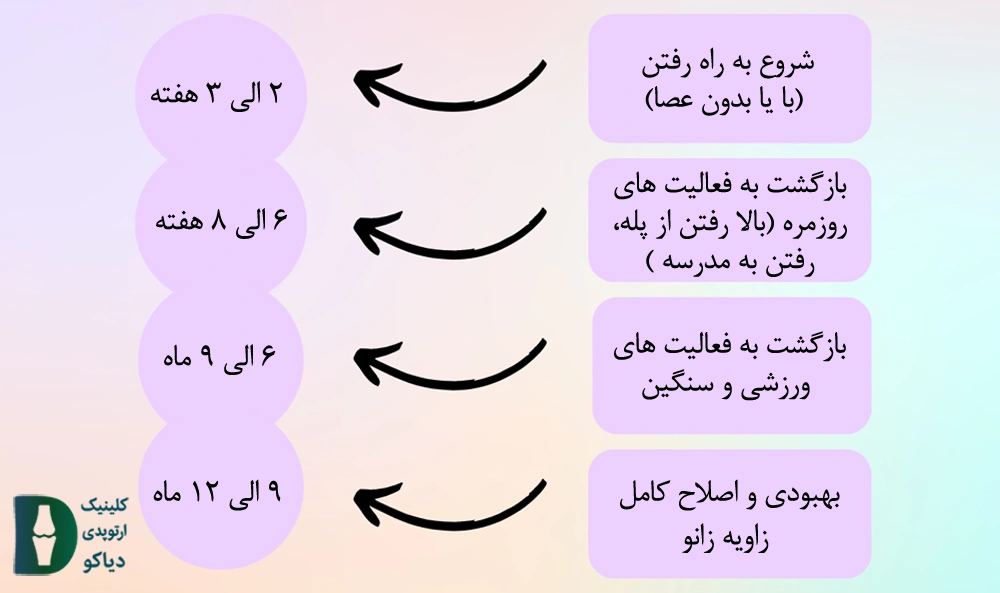

در شکل زیر زمان بازگشت به فعالیتهای مختلف شرح داده شده است. البته در نظر داشته باشید مدت زمان دقیق هریک از موارد زیر به خصوصیات بدنی فرد، سن و دیگر عوامل بستگی دارد.